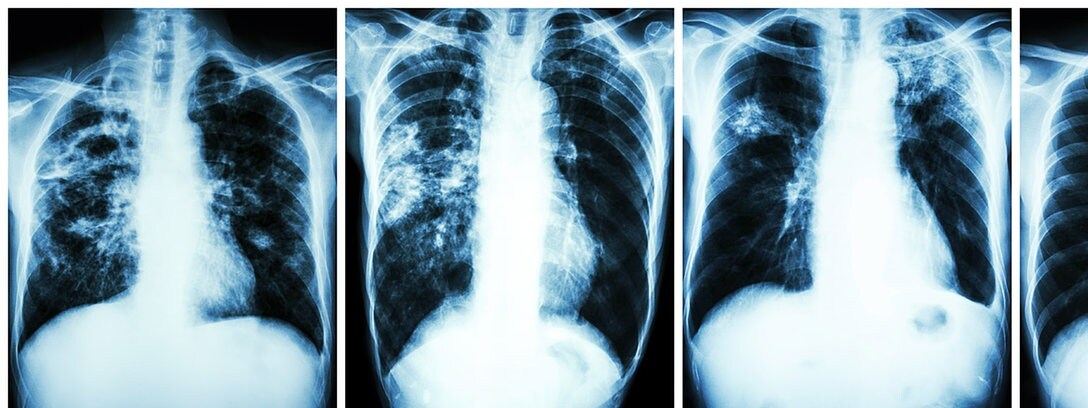

Covid 19 Langzeitfolgen Das Sind Die Auswirkungen Auf Lunge Und Herz

www.infranken.de